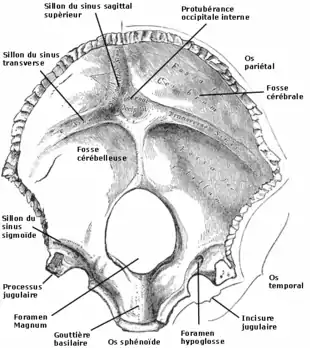

On décrit sur la face interne :

- l'écaille présente la protubérance occipitale interne d'où partent :

- le sillon du sinus sagittal supérieur,

- les sillons du sinus transverse,

- la crête occipitale.

- Ces sillons délimitent deux fosses cérébelleuses et deux fosses cérébrales.

- les jonctions latérales qui supportent :

- le sillon du sinus sigmoïde,

- le foramen de l'hypoglosse.

- à l'opposé de l'écaille le clivus, rainure plate remontant vers le sphénoïde et sur laquelle repose une partie de la moelle allongée.